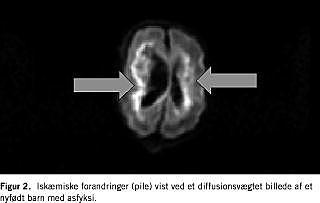

En hyppig årsag til neonatale kramper er hypoksisk-iskæmisk encefalopati. Herudover er der tale om strukturelt, metabolisk, infektiøs, abstinensudløst eller familiært betingede anfaldsfænomener. En grundig anamnese, klinisk vurdering, parakliniske undersøgelser inklusive lumbalpunktur er essentiel, men er årsagsforholdene usikre, spiller MR-skanning en vigtig rolle. Det kan dreje sig om strukturelle misdannelser, tegn på intrauterin infektion eller specifikke syndromforandringer (Figur 1 ). MR-skanning giver et væsentligt bidrag til en hurtig diagnostisk afklaring, hvilket i nogle situationer kan få behandlingsmæssige konsekvenser, allerede mens barnet ligger på neonatalafsnittet. I tilfælde af hypoksisk-iskæmisk hjernepåvirkning kan omfanget af de hypoksiske skader påvises umiddelbart efter skadens optræden med MR-skanning ved hjælp af såkaldte diffusionsoptagelser (en afbildning af vandets molekylbevægelser) [1] (Figur 2 ). Med spektroskopi kan man bedømme graden af neurontab og graden af anaerobt stofskifte [1], hvilket er vigtige prognostiske indikatorer. Undertiden afslører man med spektroskopien abnorme metabolitter, og det kan i disse situationer give en vigtig vejledning i påvisningen af en metabolisk sygdom. CT bør som hovedregel ikke anvendes i neonatalperioden undtagen i helt specielle tilfælde for at påvise store, behandlingskrævende blødninger på tidspunkter, hvor der ikke er mulighed for at foretage en MR-skanning.